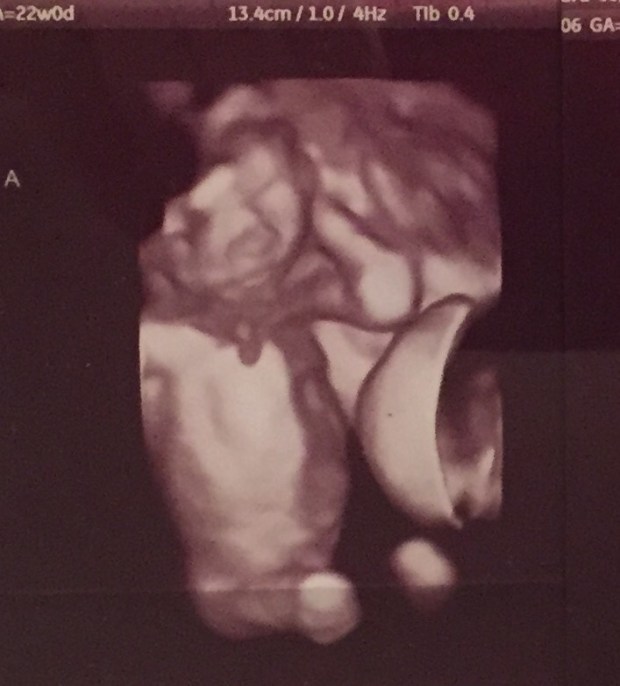

Mac and I joke now that we will never go to Vegas because odds haven’t worked in our favor. At 23 weeks, our boys wound up in full Stage 4 Twin-to-Twin Transfusion with zero warning. Oliver was the recipient – he was already in heart failure and his entire body was filled with excess fluid (hydrops). When they first pulled up the ultrasound and scanned him – I didn’t recognize him as the same baby I saw a week prior. There was a 1″ dark outline around every bone and organ. His brain was surrounded by fluid. His heart was surrounded by fluid. His belly was big, round, and his organs just seemed to float within. When they moved the ultrasound machine over to scan Greyson, he was the polar opposite. He had zero amniotic fluid (they compare it to being covered in Saran wrap) – no fluid in his belly and a nearly invisible bladder. They checked on Tommy – who was showing no signs of distress from his sick brothers – and they ran a million tests on me to see if there was a reason this all came on so quickly. When all of my tests came back normal, the incredibly tough conversations began. “What now?”